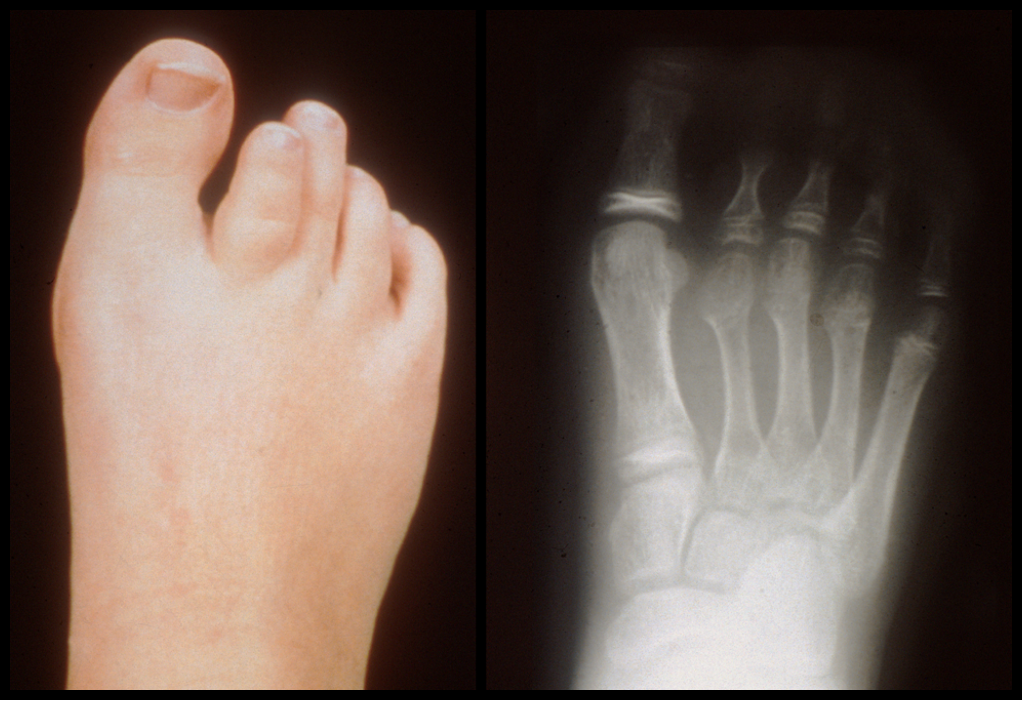

关节畸形:趾骨缩短